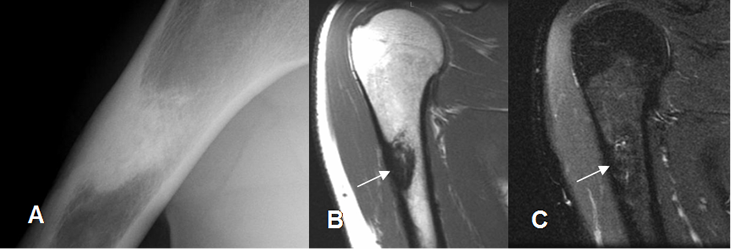

Fig 53. Enostosis.

A: Rx AP. Enostosis del húmero, con lesión densa y espiculada.

B: RM coronal en T1 y C: RM coronal en STIR. La imagen es hipointensa en ambas secuencias, por su calcificación compacta.